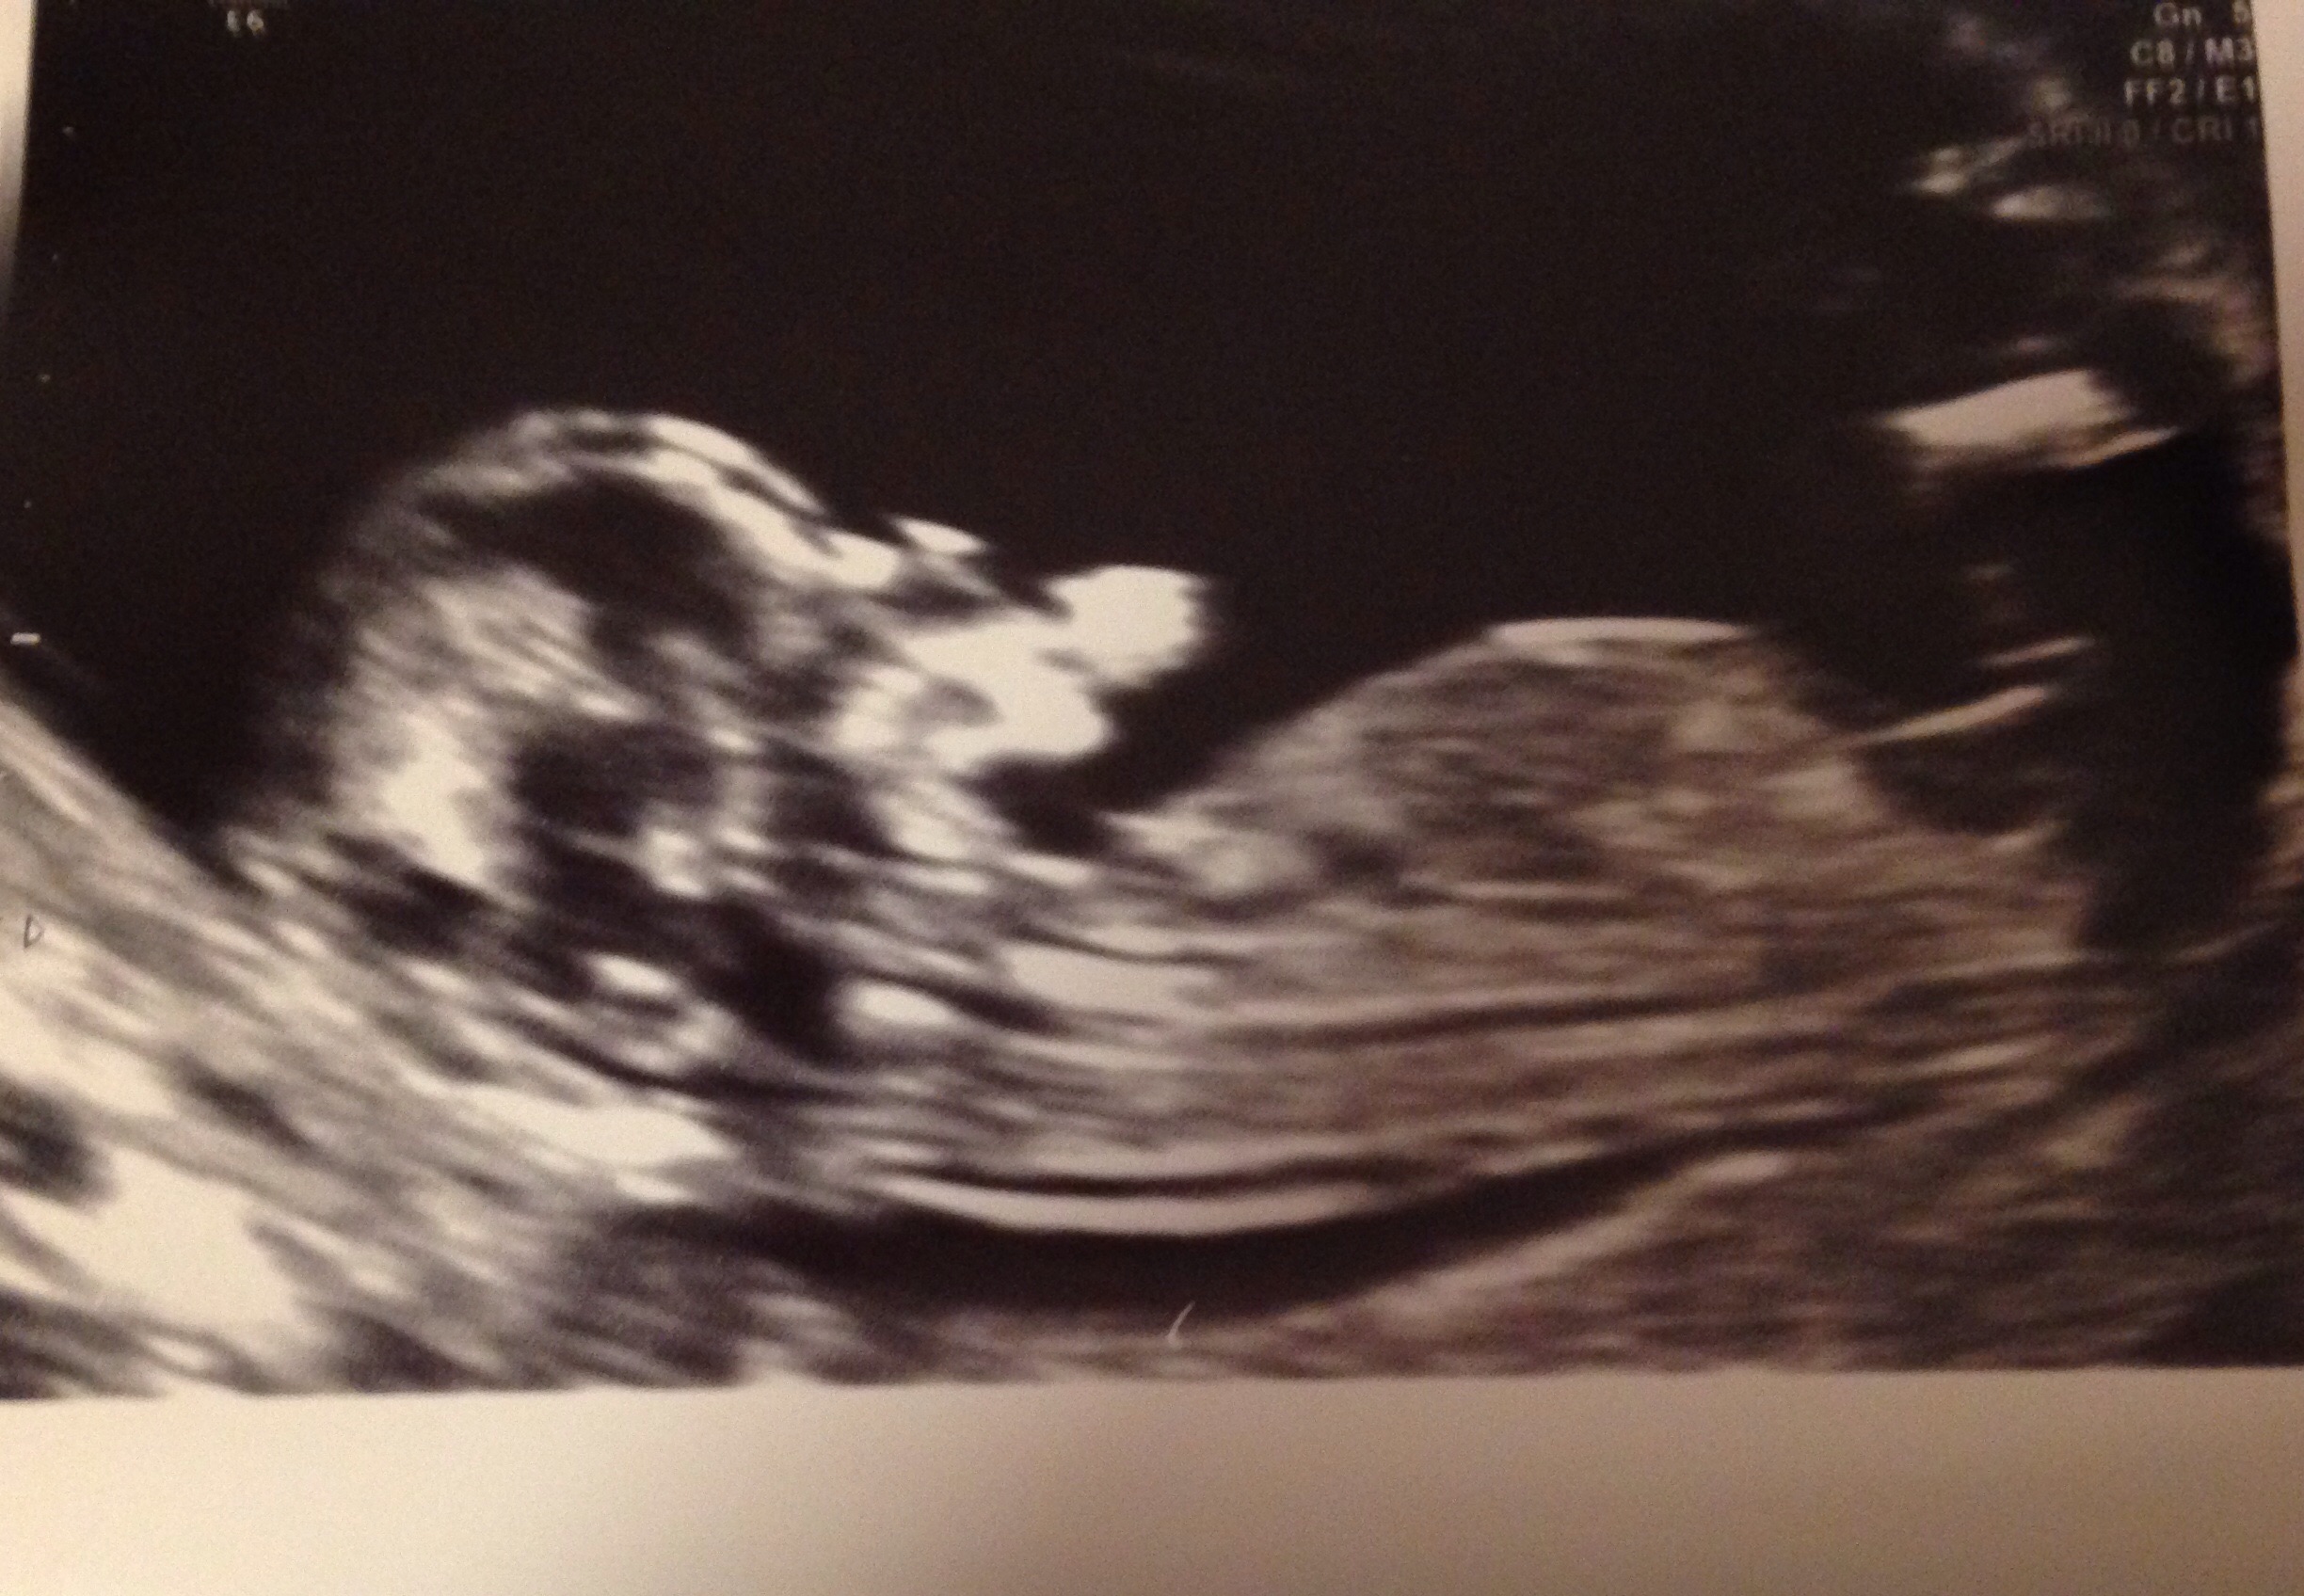

my babies scan at 12 weeks 6 days would you say boy or girl Attachment 21332